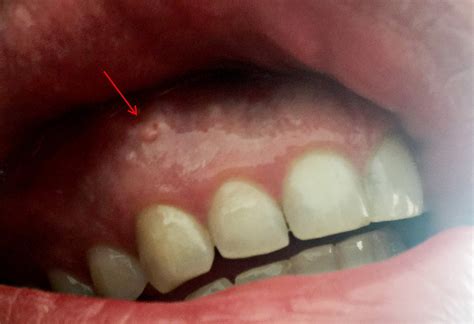

Gingival Cysts

Gingival cysts are small, fluid-filled sacs that develop on the gums. They are usually painless and can vary in size. These cysts are often benign and may resolve on their own, but in some cases, they may require surgical removal.

Oral Cancer

While less common, painless bumps on gums can sometimes be a sign of oral cancer. Oral cancer can appear as a lump, sore, or discolored patch in the mouth. It is important to note that oral cancer often does not cause pain in its early stages, making regular dental check-ups crucial for early detection.